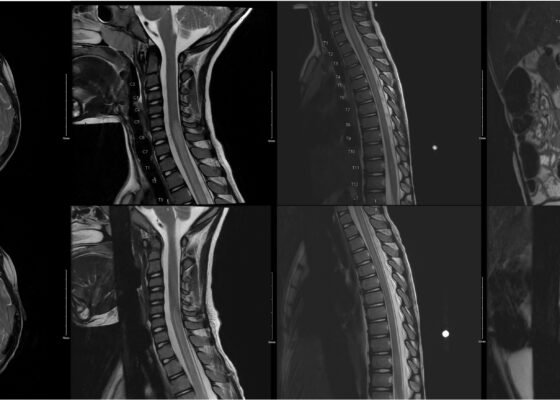

DOI: https://doi.org/10.21980/J8QQ1QAn MRI with contrast, T2 sequence was performed. In Figures a-d, the MRI of the patient’s brain and spinal cord on admission shows abnormal signals in the patient’s pons (lack of symmetrical gray-white differentiation on cross-section) along with hyperintensity (sagittally shown as brightness in what should be homogenously intense spinal cord) and significant central cord edema (with swelling seen as increased width) starting from C5 and continuing to the conus medullaris around L1/L2.